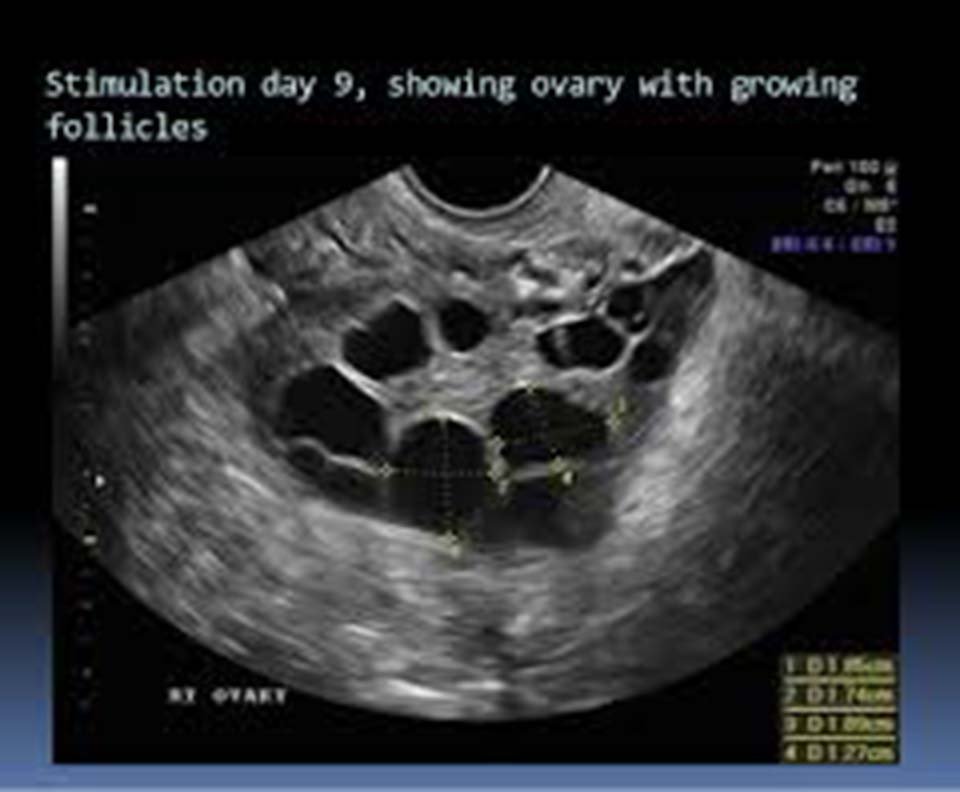

Follicle Tracking

To track the development and size of follicles in the ovaries to determine the best timing for ovulation and subsequent steps like IUI or IVF.